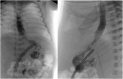

Case presentation: A 2-day-old term male was referred to our institution in extremis following attempted resuscitation with makeshift positive airway pressure ventilation in the setting of respiratory distress. Exam was notable for a distended, peritonitic abdomen, and abdominal radiograph showed massive pneumoperitoneum. Exploratory laparotomy revealed an extensive anterior gastric perforation extending from the pylorus to the esophagogastric junction, along with gross ischemia of the posterior gastric wall. The patient underwent gastrectomy with pouchless retrocolic Roux-en-Y esophagojejunostomy reconstruction. He was kept NPO (nil per os) on total parenteral nutrition for seven days. Esophagram on postoperative day 7 demonstrated patency of the esophagojejunal anastomosis without leaks, and he was transitioned to formula via nasojejunal tube feeds supplemented with vitamins and pancreatic enzymes. He was discharged home on postoperative day 45. At latest follow-up 2.9 years after surgery, his height and weight were in the 10th percentile for his age.